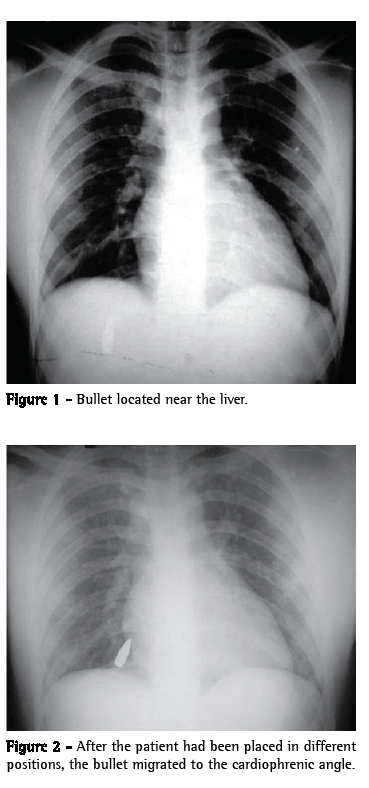

A 19-year-old male patient with a penetrating injury caused by a bullet sought treatment in the emergency room. The entry wound was located in the fourth right intercostal space, lateral to the nipple line. The patient was lucid, presented normal respiration and was hemodynamically stable. The mucosa was salmon-colored. The pulse was regular and strong. The physical examination revealed no abnormalities. An anteroposterior chest X-ray revealed a high-velocity (rifle) bullet located near the liver (Figure 1). With the patient being placed in different positions, a second anteroposterior chest X-ray and a computed tomography scan showed a change in the position of the bullet, which was now located at the right cardiophrenic angle (Figure 2). With a diagnosis of a bullet free in the pleural cavity, removal via video-assisted thoracoscopy was indicated. Under general anesthesia, the patient was intubated with a double-lumen endotracheal tube and placed in the left lateral decubitus position. The procedure started with the introduction of one 10-mm trocar and two 5-mm trocars. In the initial inspection using a 30° ­endoscope, we found only a small ecchymosis in the middle lobe and a bullet, located in the anterior cardiophrenic recess, free in the pleural cavity. The bullet was easily removed with the aid of forceps. The chest tube was left in place for 24 h, and was discharged from the hospital on postoperative day 2.